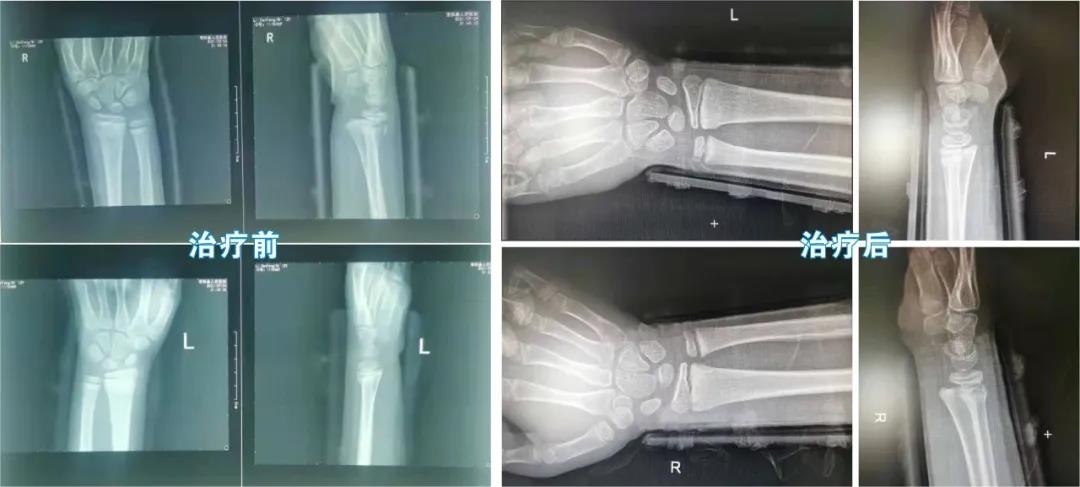

很快,黄某在家人陪伴下被送到梧州市中医医院就诊,经详细检查后,发现患者双侧腕部肿胀明显,腕关节活动受限,双腕部位呈餐叉样畸形,压痛明显。医院岭南骨伤医派专家团队马上对患者施行无痛手法复位,通过牵拉、折顶、端提等系列动作,及时、快速地完成了双侧腕关节复位。

患者在小夹板外固定后,通过C臂机透视显示:双侧桡骨远端骨折和尺桡关节脱位已经复位,骨折对位对线良好,达到预期效果。